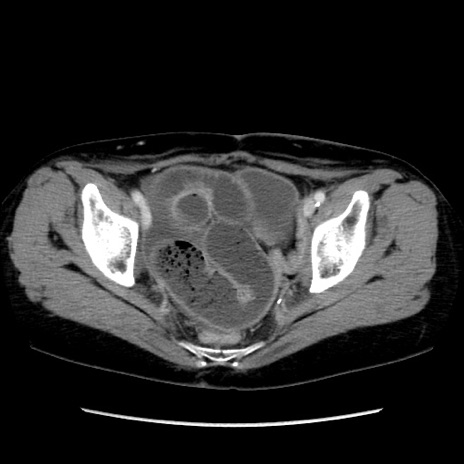

症例32(横断像)

【症例】40歳代 女性

【主訴】上腹部痛、嘔気・嘔吐

【現病歴】約9時間前頃から急に上腹部痛、嘔気、嘔吐が出現。改善しないため救急要請。

【既往歴】子宮頚癌(広汎子宮全摘術、放射線療法)、腸閉塞

【身体所見】腹部:平坦、軟、腸雑音亢進、上腹部を中心に腹部全体に圧痛あり。

【データ】WBC 8400、CRP 0.03